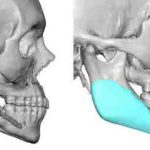

Jaw angle implants are most commonly placed through an intraoral approach without visible external scars. With bilateral posterior vestibular incisions that are up out on the cheek opposite the 2nd molar tooth, subperiosteal dissection is done to elevate the masseter muscle off of the bone. Depending upon the type of jaw angle implant being used, Read More…